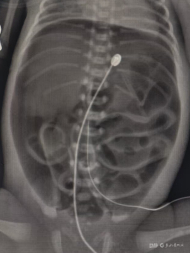

据了解,这名早产儿胎龄为30周+6天,出生后即转入新生儿重症监护室(NICU)接受监护。出生第3天,患儿出现腹部异常膨隆,经床旁X光检查提示腹腔内大量游离气体,高度怀疑消化道穿孔。该院小儿外科执行主任聂梅兰团队紧急会诊,确诊为胃破裂。

胃破裂是新生儿期严重的急腹症之一,多见于早产儿,尤其是极低出生体重儿。因胃壁肌肉层薄、发育不完善,在胃内压升高时容易发生破裂。常见原因包括胃内积气、喂养不当、感染等。临床表现以腹胀、呼吸困难、全身情况迅速恶化为特征,影像学检查可见腹腔游离气体。救治关键在于早期诊断、及时手术修补及术后综合支持治疗。